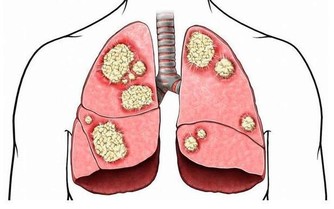

- 與某些疾病的相關性:HDL過高可能與肝臟疾病、腎臟疾病或癌症風險增加有潛在關聯,但相關機制尚待進一步研究。